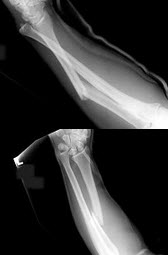

32、单项选择题

男孩,13岁,外伤后入院。结合图像,最可能的诊断是()

A.青枝骨折

B.右尺骨骨折

C.Colles骨折

D.Smith骨折

E.孟氏骨折

D.驼峰肾

女,27岁,跌倒后左手肿痛,结合X线图像,骨折类型是()

A.柯莱斯骨折